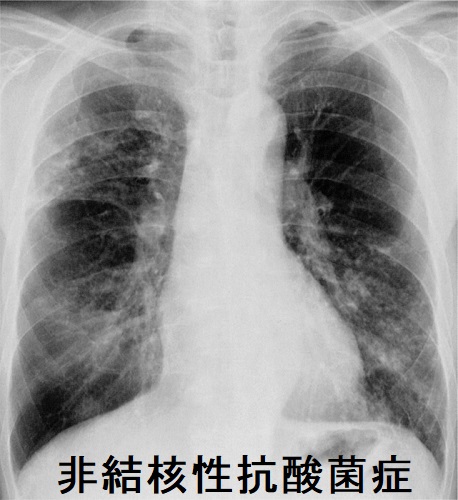

「結核菌」「ライ菌」以外の抗酸菌は「非定型抗酸菌(非結核性抗酸菌)」です。自然界に広く存在し、甲状腺機能低下症や糖尿病他免疫不全者に感染します[Infect Chemother. 2017 Nov 8;50(1):59–64.]が、人から人への感染はなく、隔離の必要はありません。

非定型抗酸菌症(非結核性抗酸菌症)は増加傾向です。肺Mycobacterium avium complex(MAC)症は、特に患者数が急増しており、結核死亡者数を超えているともされます。

非定型抗酸菌症は男性35%、女性65%、いずれも70歳代の高齢者に多い。

Mycobacterium avium complex(MAC)が約9割で最も多く、Mycobacterium kansasii、Mycobacterium abscessusがみられる。Mycobacterium kansasii、MAC、Mycobacterium intracellulareは遅速発育菌ですが、最近は難治性の迅速発育菌(M.abscessus)が増加傾向です。

遅速発育菌は寛解増悪の自然経過をとり、微熱、断続的な血痰などを繰り返します。

肺CTの線維空洞・小結節/浸潤性(円筒状)気管支拡張陰影(signet rng sign, tram line, tree in bud pattern)は非定型抗酸菌を疑う所見ですが、実際、細菌性の方が多い。空洞があると予後は悪くなります。

肺非結核性抗酸菌症の診断は、

- 喀痰抗酸菌培養検査(菌種同定を行うことにより、確定診断が得られる。自然界のものが混じるため、必ず2回以上行う)

- M.avium、M.intracellulare PCRも併用

- 痰が出ない場合や診断が難しい場合、気管支肺胞洗浄液で培養されれば確実性が高い

最近開発されたキャピリアMAC抗体(抗酸菌抗体定性)は感度70%・特異度90%(アビウム、イントラセルラーレ合わせてMAC:全体の70%)で有用。MAC抗体(抗酸菌抗体定性)は過去の非定型抗酸菌(非結核性抗酸菌)曝露によっても陽性になるので、現在の活動性を反映しません。

肺非結核性抗酸菌症は診断確定しても、必ずしも全員に治療を行う訳ではありません。空洞、塗抹陽性、血痰・喀血などがあれば積極的に治療を考慮する。

高齢者や結節性気管支拡張だけでは、経過観察になる事が多い。

多くの抗菌薬に自然耐性があるため、薬が効きにくい。治療はクラリスロマイシン+抗結核薬2 剤(リファンピシン・エタンブトール)の3 剤併用療法が基本ですが、多くは治療抵抗性。リファンピシンは薬剤性甲状腺機能低下症の原因です。

非定型抗酸菌の1.8%に肺癌を合併するとされ、注意を要します。

72歳のインスリン依存性糖尿病+甲状腺機能低下症/橋本病患者におきたMycobacterium avium intracellulareを起因菌とする急性化膿性甲状腺炎の報告があります[J Endocrinol Invest. 1994 Feb;17(2):133-4.]